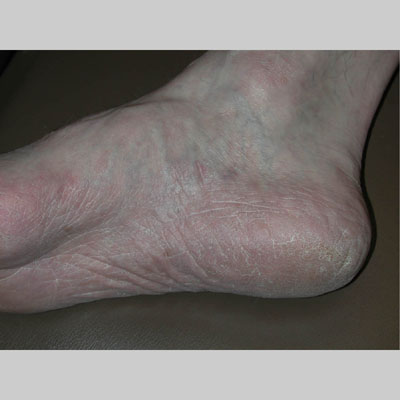

Chronic Hyperkeratotic Type.

Usually bilateral with patchy or diffuse scaling limited to the thick skin, soles, and the lateral and medial aspects of the feet, this is also known as “moccasin-type” tinea pedis. T. rubrum, the most common etiology, produces very few minute vesicles, leaving collarettes of scale less than 2 mm in diameter. Erythema is variable.

Unilateral tinea manuum commonly occurs in association with hyperkeratotic tinea pedis, resulting in the “two feet-one hand syndrome” . When tinea manus extend to the dorsum of a hand, it assumes the clinical pattern of tinea corporis . Oral antifungals are often required for treatment due to the high incidence of concomitant onychomycosis and relapse.